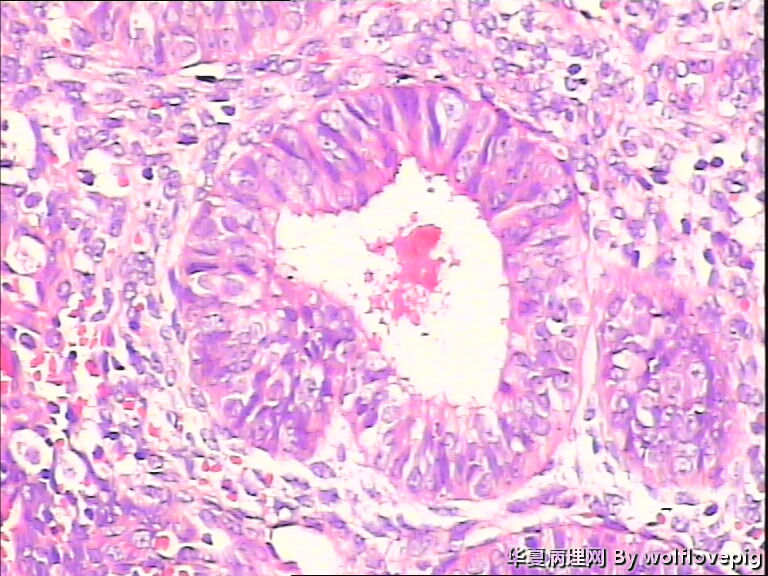

求助,子宫内膜!

48y

简单型增生伴轻度非典型增生

子宫内膜复杂性非典型增生

复杂性增生伴轻度非典

复杂性伴非典型增生

复杂性非典型增生(EIN)

简单型增生过长,48岁的女性,可能是转型的时候,而且内膜的共壁不是很明显,腺管的上皮增生层次也不是很明显,腺、间质比例较正常,所以有一点的异型不用太担心。同时刮宫既是诊断、又是治疗,可以妇科激素用药。

个人认为有不典型增生。

复杂性非典型增生

子宫内膜单纯性增生

子宫内膜复杂性非典型增生(有没有癌变,待制作优良的切片再诊断吧)。